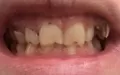

Волнуют мои зубы. Мне кажется, что мои зубы находятся в крайне запущенном состоянии. Как привести мои зубы в приемлемый вид? Мне кажется, что запломбированные зубы плохо выглядят. На верхней левой четверке выпала пломба.

Стесняюсь показывать свои зубы стоматологу. Чищу зубы ежедневно по 2 раза в день, но возможно, что чищу неверно.

Ваши зубы скорее всего требуют срочного лечения. Где-то возможно хроническое воспаление (периодонтит), а где-то и пульпит (воспаление нерва).